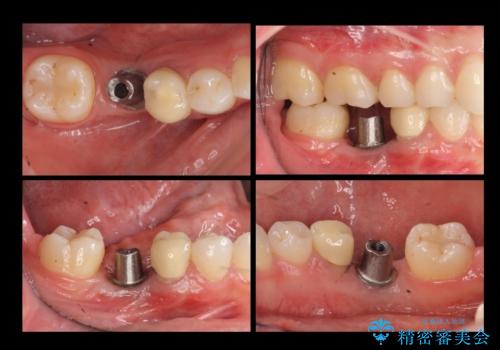

奥歯のインプラント

- 右下6番が保存不可能だったため、やむなく抜歯しました。

インプラント治療をご希望されたため、植立を行いました。

インプラントを入れる際、部分的に骨を増やす処置を行っています。